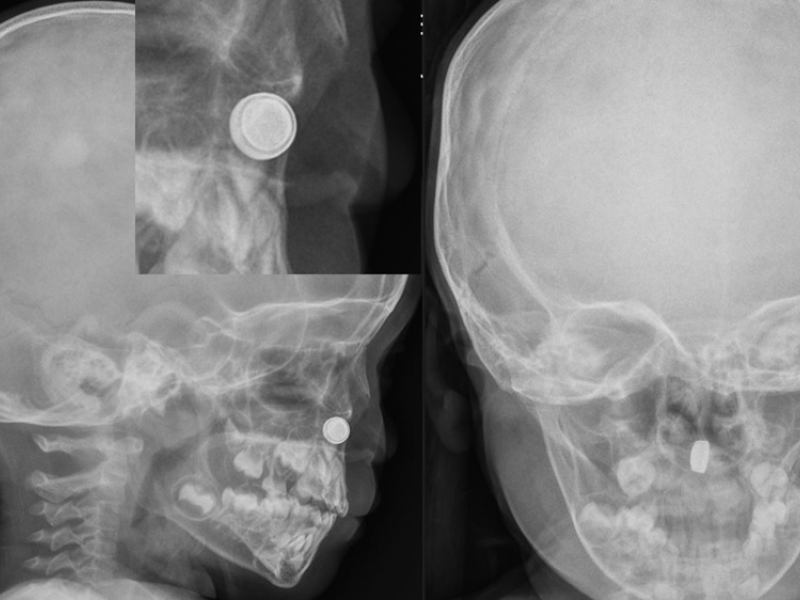

A 20 year old male presents to the emergency department via